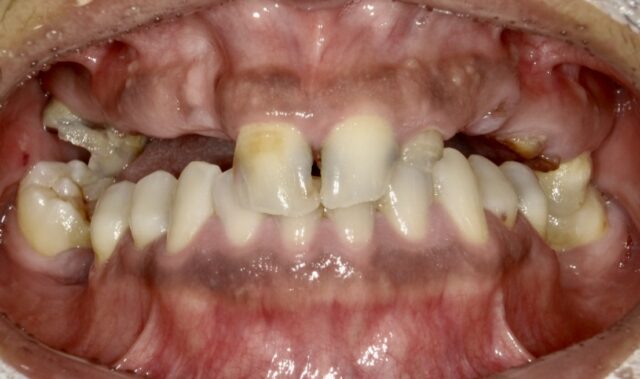

BEFORE

ずっと悪いのを放置し続けていたが、今回きちんと治療したいとの事できちんと通院。

術前